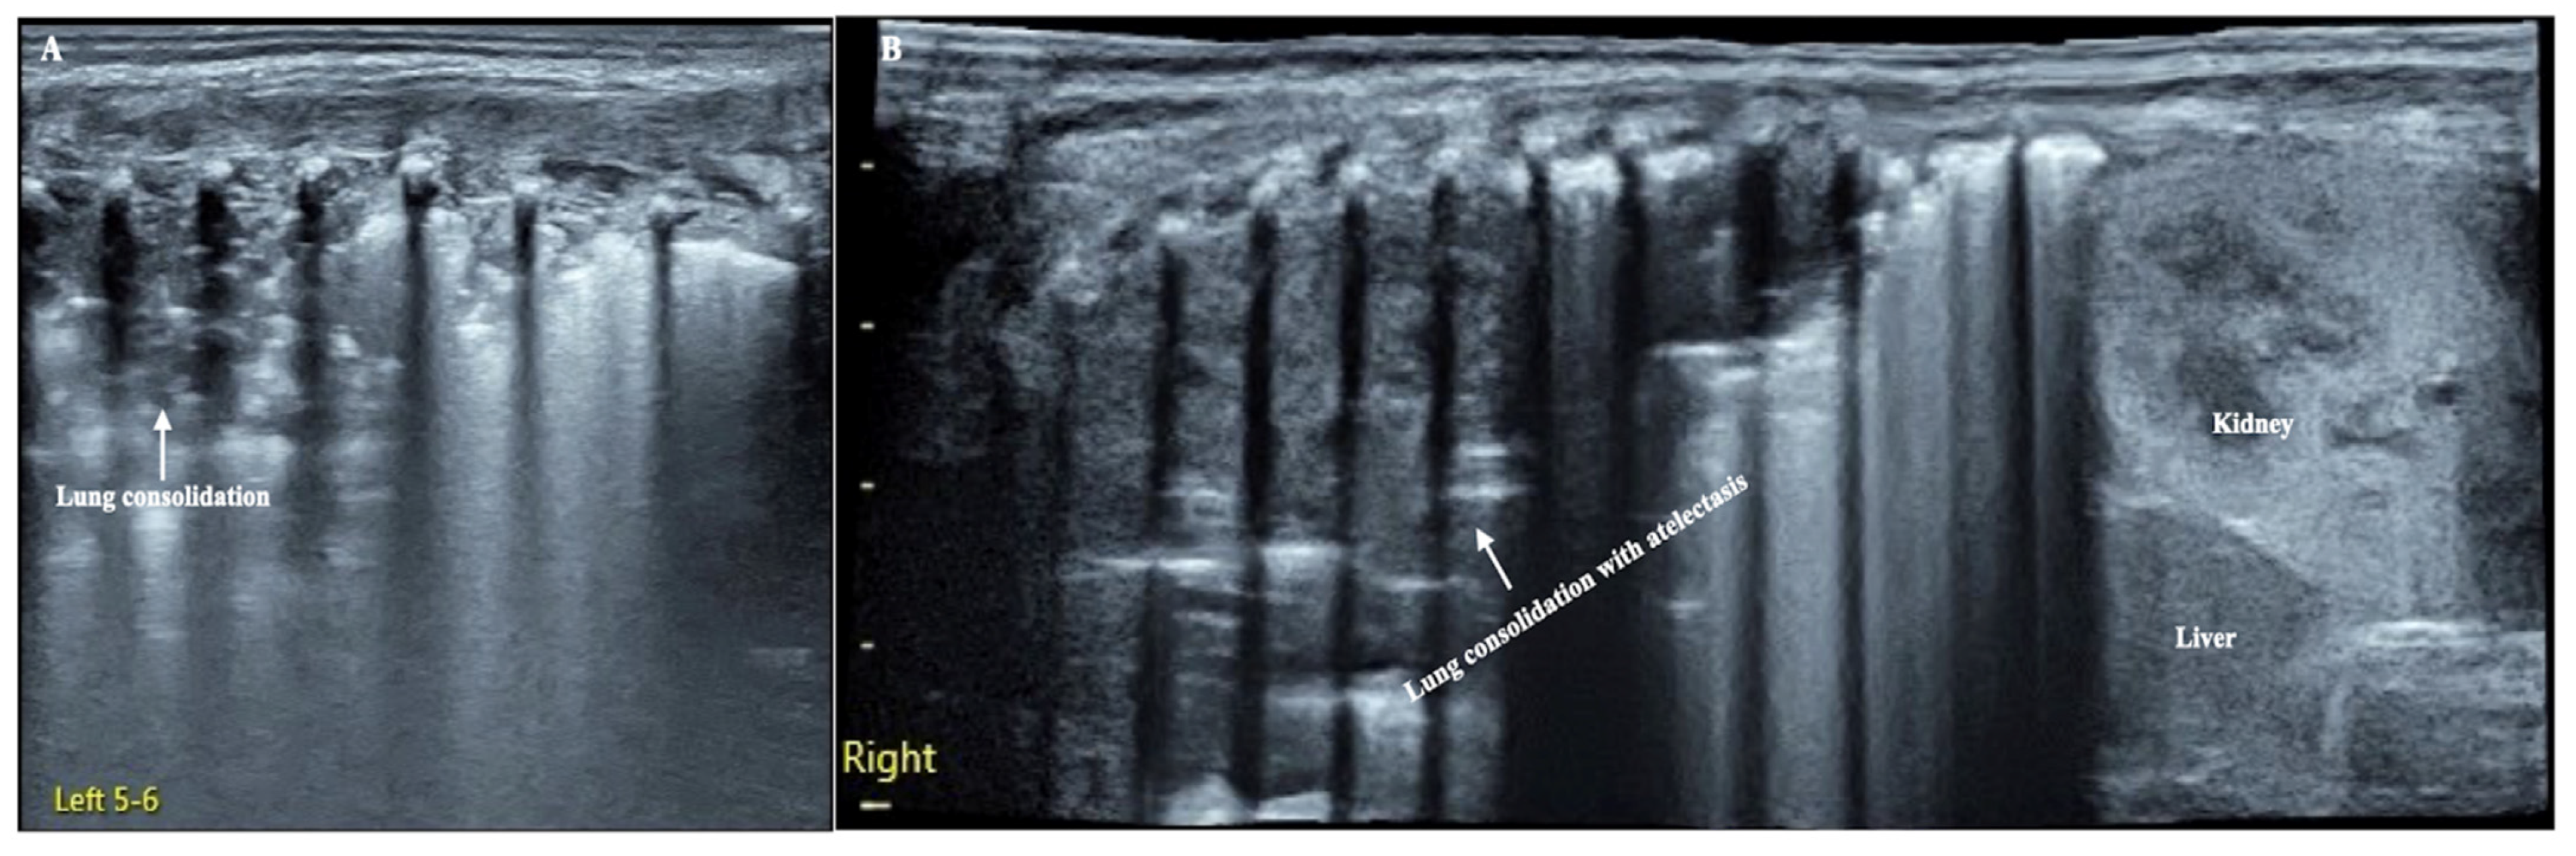

Figure 1.

LUS manifestation of the patient. (A): Left lung. Large-area lung consolidation with jagged boundaries (mainly involved the upper lung field), while in the lower lung field, lung edema and subpleural consolidation were predominant, which indicate the presence of pneumonia [1]. (B): Right lung (extended view). Lung consolidation was almost involved in the whole lung field with regular edges, and there was almost no bronchial aeration in the consolidation area, which means that the entire right lung was atelectatic [2].

The patient was a male premature infant delivered by cesarean section because of placental abruption at gestational age 28 weeks with a birth weight of 900 g. The infant was hospitalized at the NICU due to severe respiratory distress and subsequently complicated with diffuse intravascular coagulation (DIC) at the late stage of hyperfibrinolysis. A blood examination showed a white blood cell count (WBC) of 29.3 × 109/L and a c-reactive protein (CRP) of >150 mg/L (normally, <2.0 mg/L) at 4 h after birth. The patient’s condition stabilized after 10 days of invasive mechanical ventilation, anti-DIC and broad-spectrum antibiotic treatment. However, from the 14th day after birth, the infant had persistent fever (a temperature higher than 38 °C), and dyspnea reoccurred. The fever lasted for more than two weeks with a temperature >38 °C (highest 38.8 °C); the WBC count was elevated between a total of (21~29) × 109/L with a significantly elevated neutrophil ratio (>80%); the CRP increased (>150 mg/L for more than 2 weeks) for more than three weeks; the platelet count continued to decrease for more than 2 weeks (minimum <10 × 109/L); and three blood cultures and three deep sputum cultures and peripherally inserted central catheter (PICC) tip cultures showed no pathogenic bacterial growth. An LUS examination showed a large area of lung consolidation forming significant atelectasis in both lungs. The left lung mainly involved the upper lung field, while the right lung was almost consolidated in all lung fields (Figure 1). There was almost no bronchial inflation in the consolidation area, but a Doppler ultrasound showed that blood supply was still present well in the consolidated lung fields (Figure 2). This is very different from the normal lung images, which present as a bamboo sign on a B-mode ultrasound (Figure 3). During this period, the infant successively received meropenem, imipenem, linezolid, the fourth generation of cephalosporin, metronidazole and other antibiotics, and his condition still did not improve. Although both mycoplasma and chlamydia antibody/antigen tests were negative, when the antibiotics were adjusted to macrolide antibiotics (azithromycin) on day 28 postnatally, the temperature of the infant fell below 38 °C that day, and then, the temperature remained normal. Then, with the informed consent of the parents, blood samples were collected for metagenomic next-generation sequencing (mNGS) testing for pathogens, and the detection result confirmed legionella pneumophila infection. Therefore, the patient continued to receive azithromycin. The temperature remained normal, and the WBC, platelet and CRP levels gradually returned to the normal range within a week. The LUS showed that the scope of the lung consolidation gradually narrowed until it disappeared completely after 20 days (Figure 4). The total treatment period lasted for nearly 4 weeks, and the patient was discharged on the 70th day after birth, with a weight of 2620 g at that time. The infant was followed up for nearly 12 months and experienced normal growth. Over the past decade, LUS has been widely used in the diagnosis and differential diagnosis of neonatal lung diseases [3,4], including neonatal pneumonia [5,6,7]. LUS has a number of advantages over CXR; it should serve as a complementary diagnostic method in providing accurate, timely and reliable information [8,9]. The major finding of the LUS examination in this patient was the large-area consolidation in the bilateral lungs. There were a few air bronchograms in the consolidation area of the left lung but no air in the consolidated area of his whole right lung, which meant serious atelectasis (Figure 1). However, Doppler ultrasonography showed that there was still good blood supply in the lung tissues with consolidation and atelectasis (Figure 2). The presence of blood supply is a prerequisite for the consolidation and atelectasis of lung tissue to recover to normal [2].